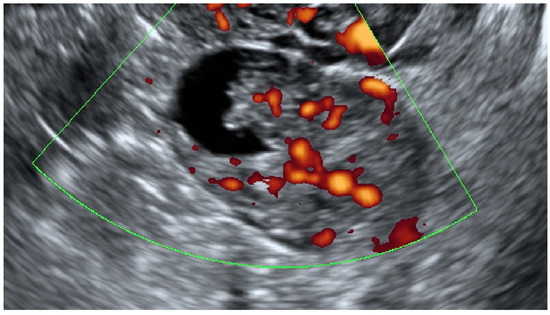

| Color Score | ||||

| 1 | 33 (53.2) | 6 (23.1) | 4 (20) | 0.0009 |

| 2 | 13 (21) | 13 (50) | 4 (20) | |

| 3 | 15 (24.2) | 5 (19.2) | 8 (40) | |

| 4 | 1 (1.6) | 2 (7.7) | 4 (20) |